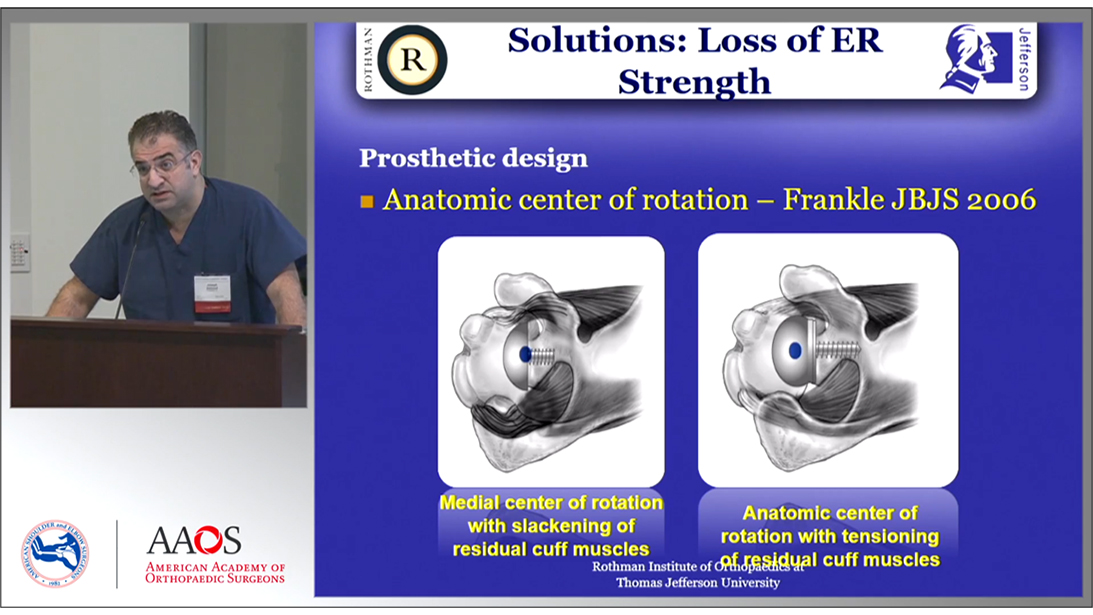

Reverse Shoulder Arthroplasty

Course Directors

Bradford O. Parsons, MD

Samer S. Hasan, MD, PhD

Topics include: biomechanics and history of RSA, expanded indications for RSA, postoperative rehabilitation and complications, failed RSA, and indications for revision surgery.

50 CME Credits

5 Modules, 20 Lessons